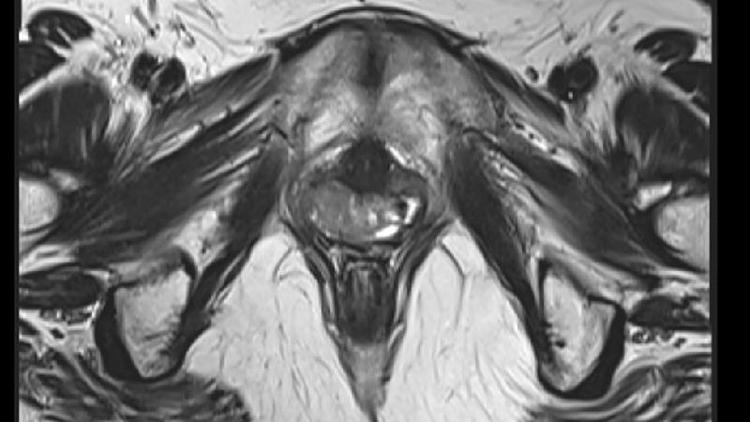

"Podemos pedir um exame p�lvico, de ultrassom e tamb�m um teste gen�tico para verificar se a paciente tem cromossomos XX", explica Claudia Takano, coordenadora do ambulat�rio de malforma��es genitais da Universidade Federal de S�o Paulo (Unifesp), o �nico que trata a s�ndrome pelo SUS (Sistema �nico de Sa�de).

Alguns exames de imagem ajudam a diagnosticar a s�ndrome